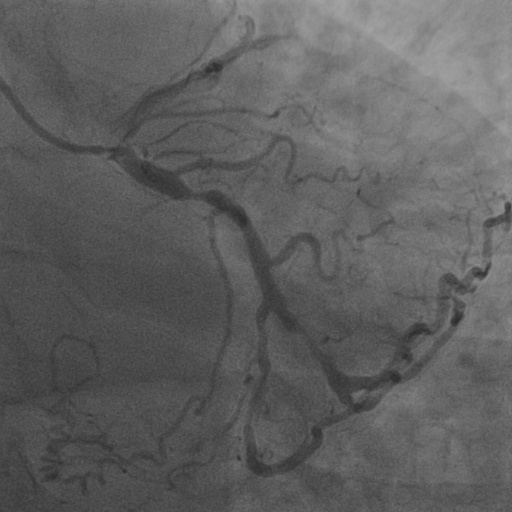

| Image | Ground truth | Video frame | Ground truth | Video frame | Ground truth |

| XCAD [33] | CADICA [19] | Our XACV dataset | |||

4.1 XACV Dataset

We collect 111 complete records of coronary artery X-ray videos, encompassing the injection, flow through the blood vessels around the heart, and dissipation of the contrast agent. Subsequently, we establish the XACV (X-ray Angiography Coronary Video) dataset. Each video consists of varying numbers of high-resolution coronary artery X-ray images. We invite experienced radiologists to annotate the vascular regions, focusing on one or two frames where the contrast agent is most prominent in each video. The XCAD dataset contains only a single image, and the CADICA video dataset does not provide corresponding ground truth. Therefore, in the following experiments, we conduct all the analyses on our collected XACV dataset and the corresponding GT for each sequence. In Figure 5, we show that compared to other publicly available datasets, XCAD [33] and CADICA [19], our dataset exhibits finer annotations in the vascular regions, providing an advantage for future related tasks. The development and use of our dataset have been approved by our institution’s IRB.